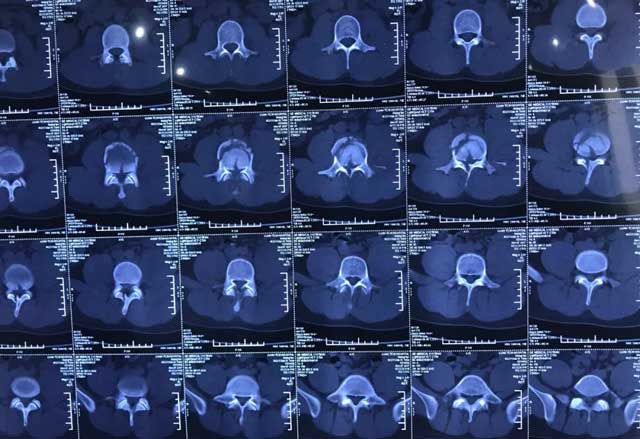

據(jù)了解,磁共振成像技術(shù)是利用人體組織中H原子核磁共振原理進(jìn)行成像的檢查技術(shù),是繼CT后醫(yī)學(xué)影像學(xué)的又一重大技術(shù)進(jìn)步,現(xiàn)已成為先進(jìn)醫(yī)學(xué)影像檢查的主流核心技術(shù)之一。永林醫(yī)院引進(jìn)的新一代聯(lián)影全數(shù)字超導(dǎo)磁共振成像系統(tǒng)具有掃描時間短、成像速度快、圖像精度高、覆蓋范圍廣、功能齊全、綠色無輻射等優(yōu)點(diǎn),可為患者進(jìn)行全身各部位的高質(zhì)量掃描,為疾病的早發(fā)現(xiàn)、早診斷、早治療提供重要科學(xué)依據(jù)。尤其在神經(jīng)系統(tǒng)病變、腫瘤性病變、感染性病變、血管性病變、代謝性病變、先天畸形以及創(chuàng)傷診斷等方面,具有更高的敏感性和特異性;對顱腦、脊椎、關(guān)節(jié)病變的顯示優(yōu)于CT,檢查不存在骨性偽影問題,在醫(yī)學(xué)檢查和科研領(lǐng)域得到廣泛應(yīng)用。